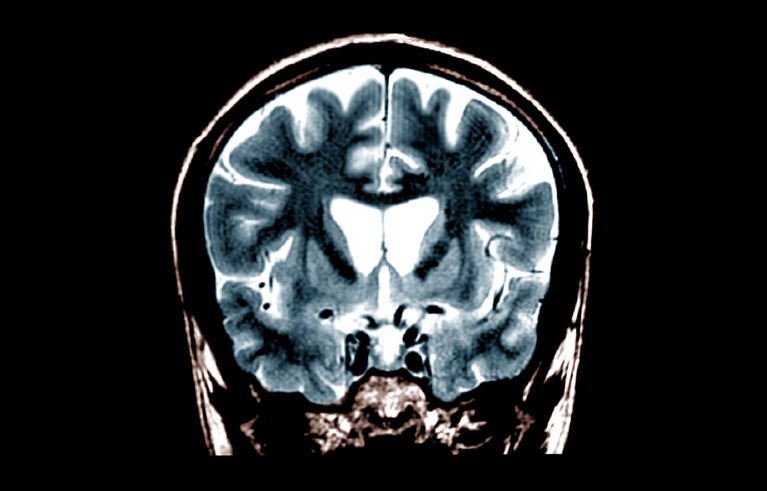

A brain scan of a person with Huntington’s disease, which causes a loss of brain volume as neurons are killed off by the accumulation of a mutant protein.Credit: Zephyr/SPL